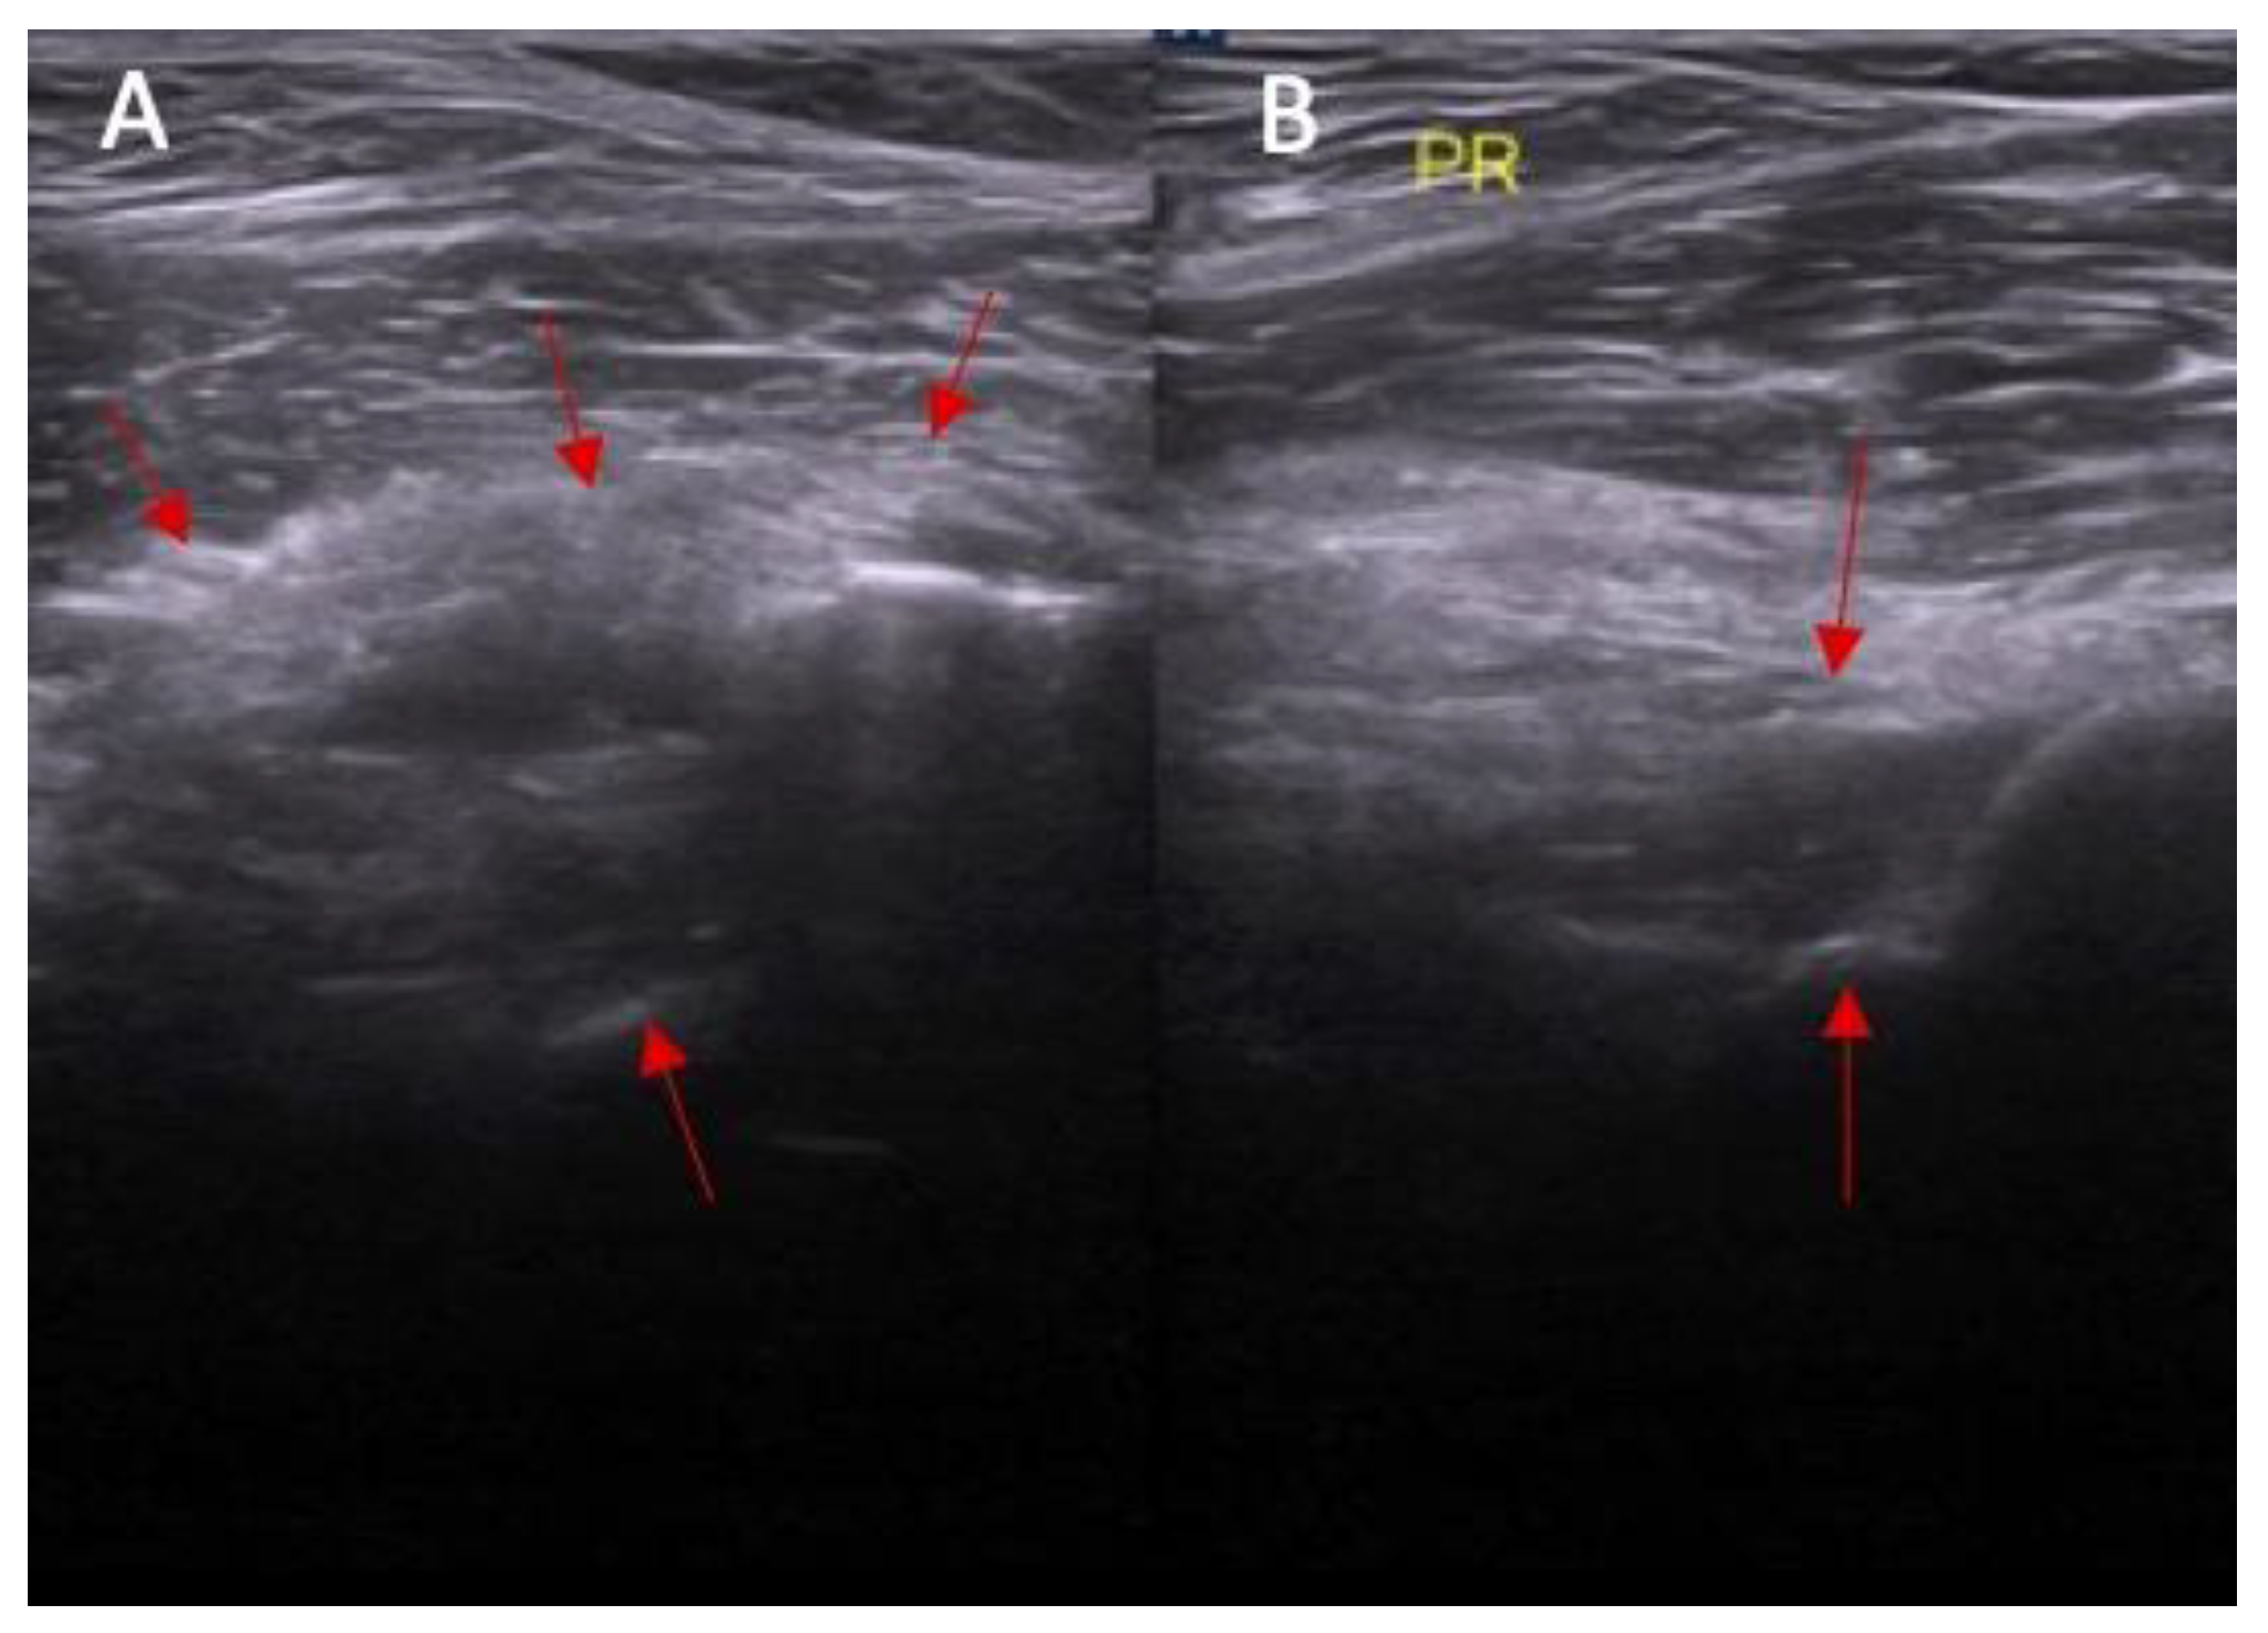

- Dynamic instability—patient is in supine position with a knee flexion of 90 degrees. The transducer is applied along the sagittal plane parallel to the longitudinal axis of patellar ligament with dynamic anterior drawer test.

2.1. Part I—Anatomical Study

- Dynamic instability in anterior drawer test with range from 0 to 2 mm, 3 to 4 mm, and ≥5 mm.

3.1. Part I—Anatomical Study